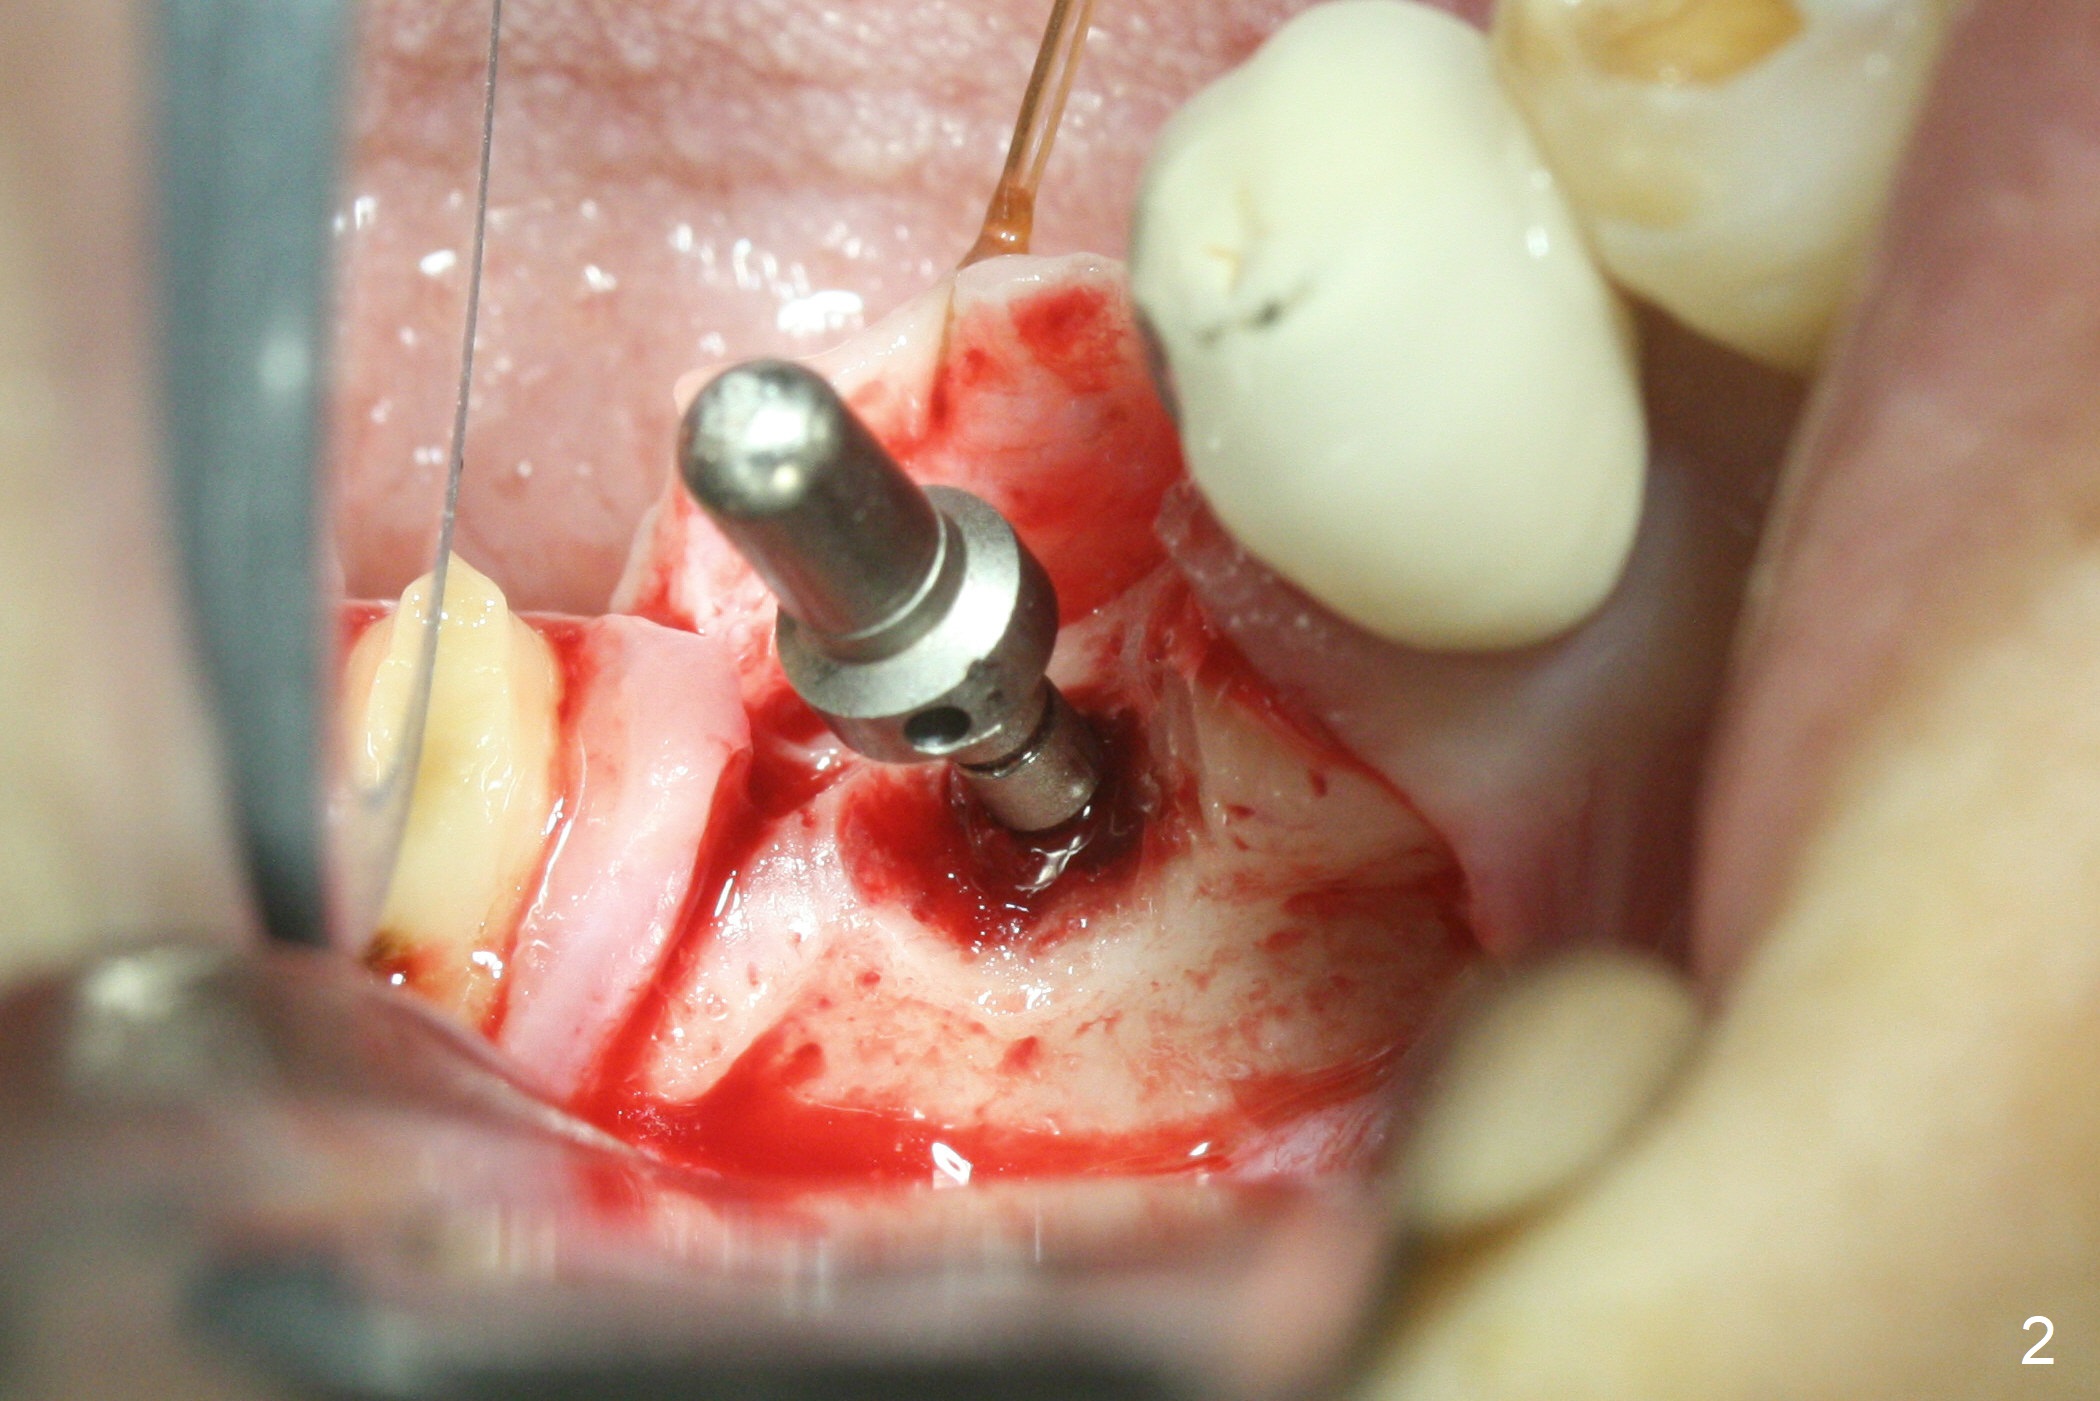

The apparently narrow ridge at #30 before bridge sectioning (Fig.1) is confirmed with incision (Fig.2). Following ridge reduction, osteotomy is initiated with 2 mm pilot drill (Fig.3). When a 3.8x12 mm SM narrow implant is placed with 40 Ncm, there is 1-2 mm cortical bone buccolingually (Fig.4,5). The thick cortices do not seem to be easy to be bent, i.e., expanded. RCT is finished at #31 one month post implant placement (Fig.6,7), the flattened ridge appears to have started to undergo remodeling. Ridge reduction makes it possible for the implant to remain subcrestal postop (Fig.4). The bone surrounding the implant may reduce the likelihood of implant fracture. The crowns at #30 and 31will be fabricated together with light occlusion at #30. In fact the splinted provisional dislodges. There appears dense bone formation 3 months postop (Fig.8 *). The drawback of using a SM narrow implant is that a narrow abutment has to be used (4.8x4(4.5) mm). The implant crown is dislodged immediately after the patient finishes lunch. Following recementation, the occlusion is reduced. In fact, UF or IBS has no such drawback: the implant could be small, but the abutment could be large. One year post cementation, the crown at #31 needs recementation (Fig.9); the bone density next to the coronal implant increases (*).